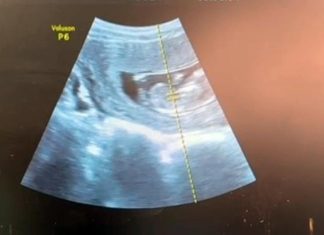

Chist ovarian gigant la o pacientă însărcinată. Intervenție laparoscopică reușită la Spitalul Onești

O intervenție chirurgicală laparoscopică complexă a fost realizată cu succes la Spitalul Municipal „Sfântul Ierarh Dr. Luca” din Onești, în cazul unei paciente însărcinate...